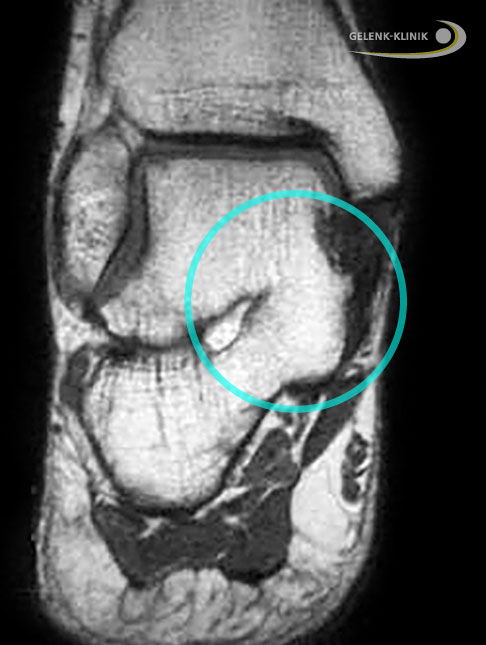

Magnetresonanztomographie (MRT) bei einem Patienten mit kompletter Koalition zwischen Sprungbein und Fersenbein (Kreis). Blick von hinten auf die Ferse: Rechts besteht eine nicht normale Verbindung der beiden Knochen. Man spricht von einer talokalkanearen Koalition. © Gelenk-Klinik